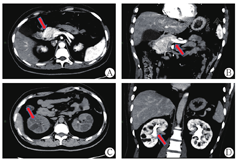

患者男,29岁,未婚,身高165 cm,体质量55 kg,体质量指数20.2 kg/m2。因"发现肝功异常、血红蛋白升高10年余"于2021年6月8日入本院肝病中心一科。患者10年余前体检发现肝功能异常伴血红蛋白升高,辗转多家医院检测,行相应检测(表1)未明确诊断。既往发现血糖升高2年,口服阿卡波糖治疗。否认饮酒病史,否认家族中有类似病史患者。查体:体温35.6℃,血压135/83 mmHg(1 mmHg = 0.133 3 kPa),呼吸20次/min,神志清楚,皮肤巩膜无黄染,心肺未见异常,腹软,肝脾未扪及,双下肢无水肿。实验室检查:碱性磷酸酶187 U/L,γ-谷氨酰转移酶226 U/L,其余肝、肾功能指标基本正常;B超提示不均质性脂肪肝,CT提示胰腺发育缺陷,胰体、胰尾缺失,双肾多发囊肿(图1)。近10年肝功能和辅助检查结果见表1。患者于2010年、2015年及2021年3次肝活检结果除提示肝脏脂肪变外无其他异常(图2)。基因检测提示HNF1B基因exon 1-9杂合缺失(图3)。最终诊断肾囊肿和糖尿病综合征。随后对其父母及姐姐的基因检测未见基因突变(图4)。

注:图中箭头所示胰腺发育缺陷,胰体、胰尾缺失,双肾多发囊肿